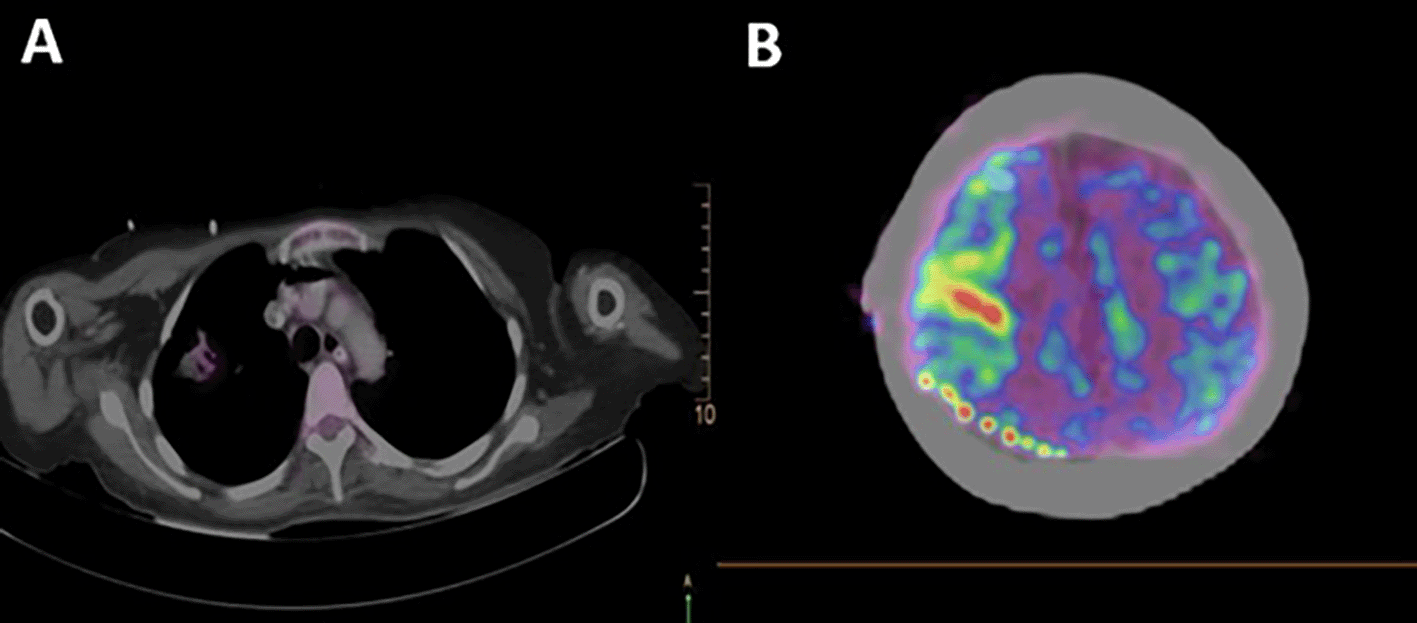

A total body 18F-fluorodeoxyglucose positron emission tomography (18F-FDG PET-CT) was performed on the patient with a GEMINI TF64 equipment in helical mode. It revealed severe hypermetabolism in the anterior segment of the right lung upper lobe (SUVmax: 5.47) and at the right precentral cerebral sulcus. These findings were suggestive of pulmonary neoplasia with leptomeningeal metastases (Figure 2).